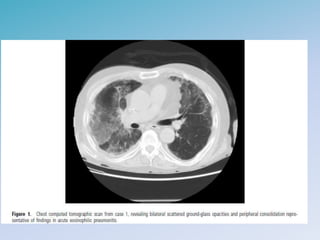

PNEUMONIA EOSINOFILICA AGUDA

• Rara, jovens previamente saudaveis

• Exposicao ambiental, tabagismo e uso de medicacoes

• Febre é sintoma mais comum (< 30 dias) com eosinofilia no LBA (>

25%) descartando outras causas

• Histopatologico: infiltracao de eosinofilos e macrofagos no

intersticio e espacos alveolares. Podem formar microabscessos

PNEUMONIA EOSINOFILICA AGUDA •Rara, jovens previamente saudaveis • Exposicao ambiental, tabagismo e uso de medicacoes • Febre é sintoma mais comum (< 30 dias) com eosinofilia no LBA (> 25%) descartando outras causas • Histopatologico: infiltracao de eosinofilos e macrofagos no intersticio e espacos alveolares. Podem formar microabscessos